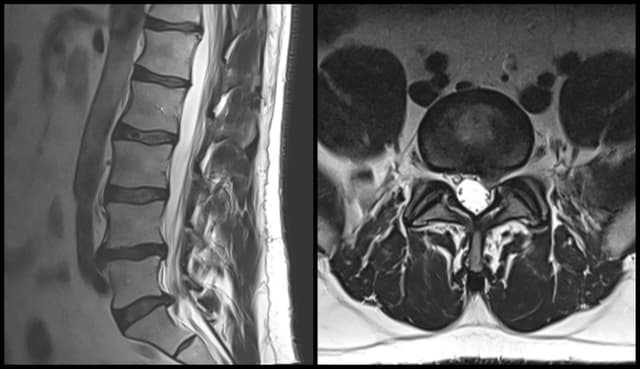

L5-S1 Microdiscectomy

Imaging

Pre-op